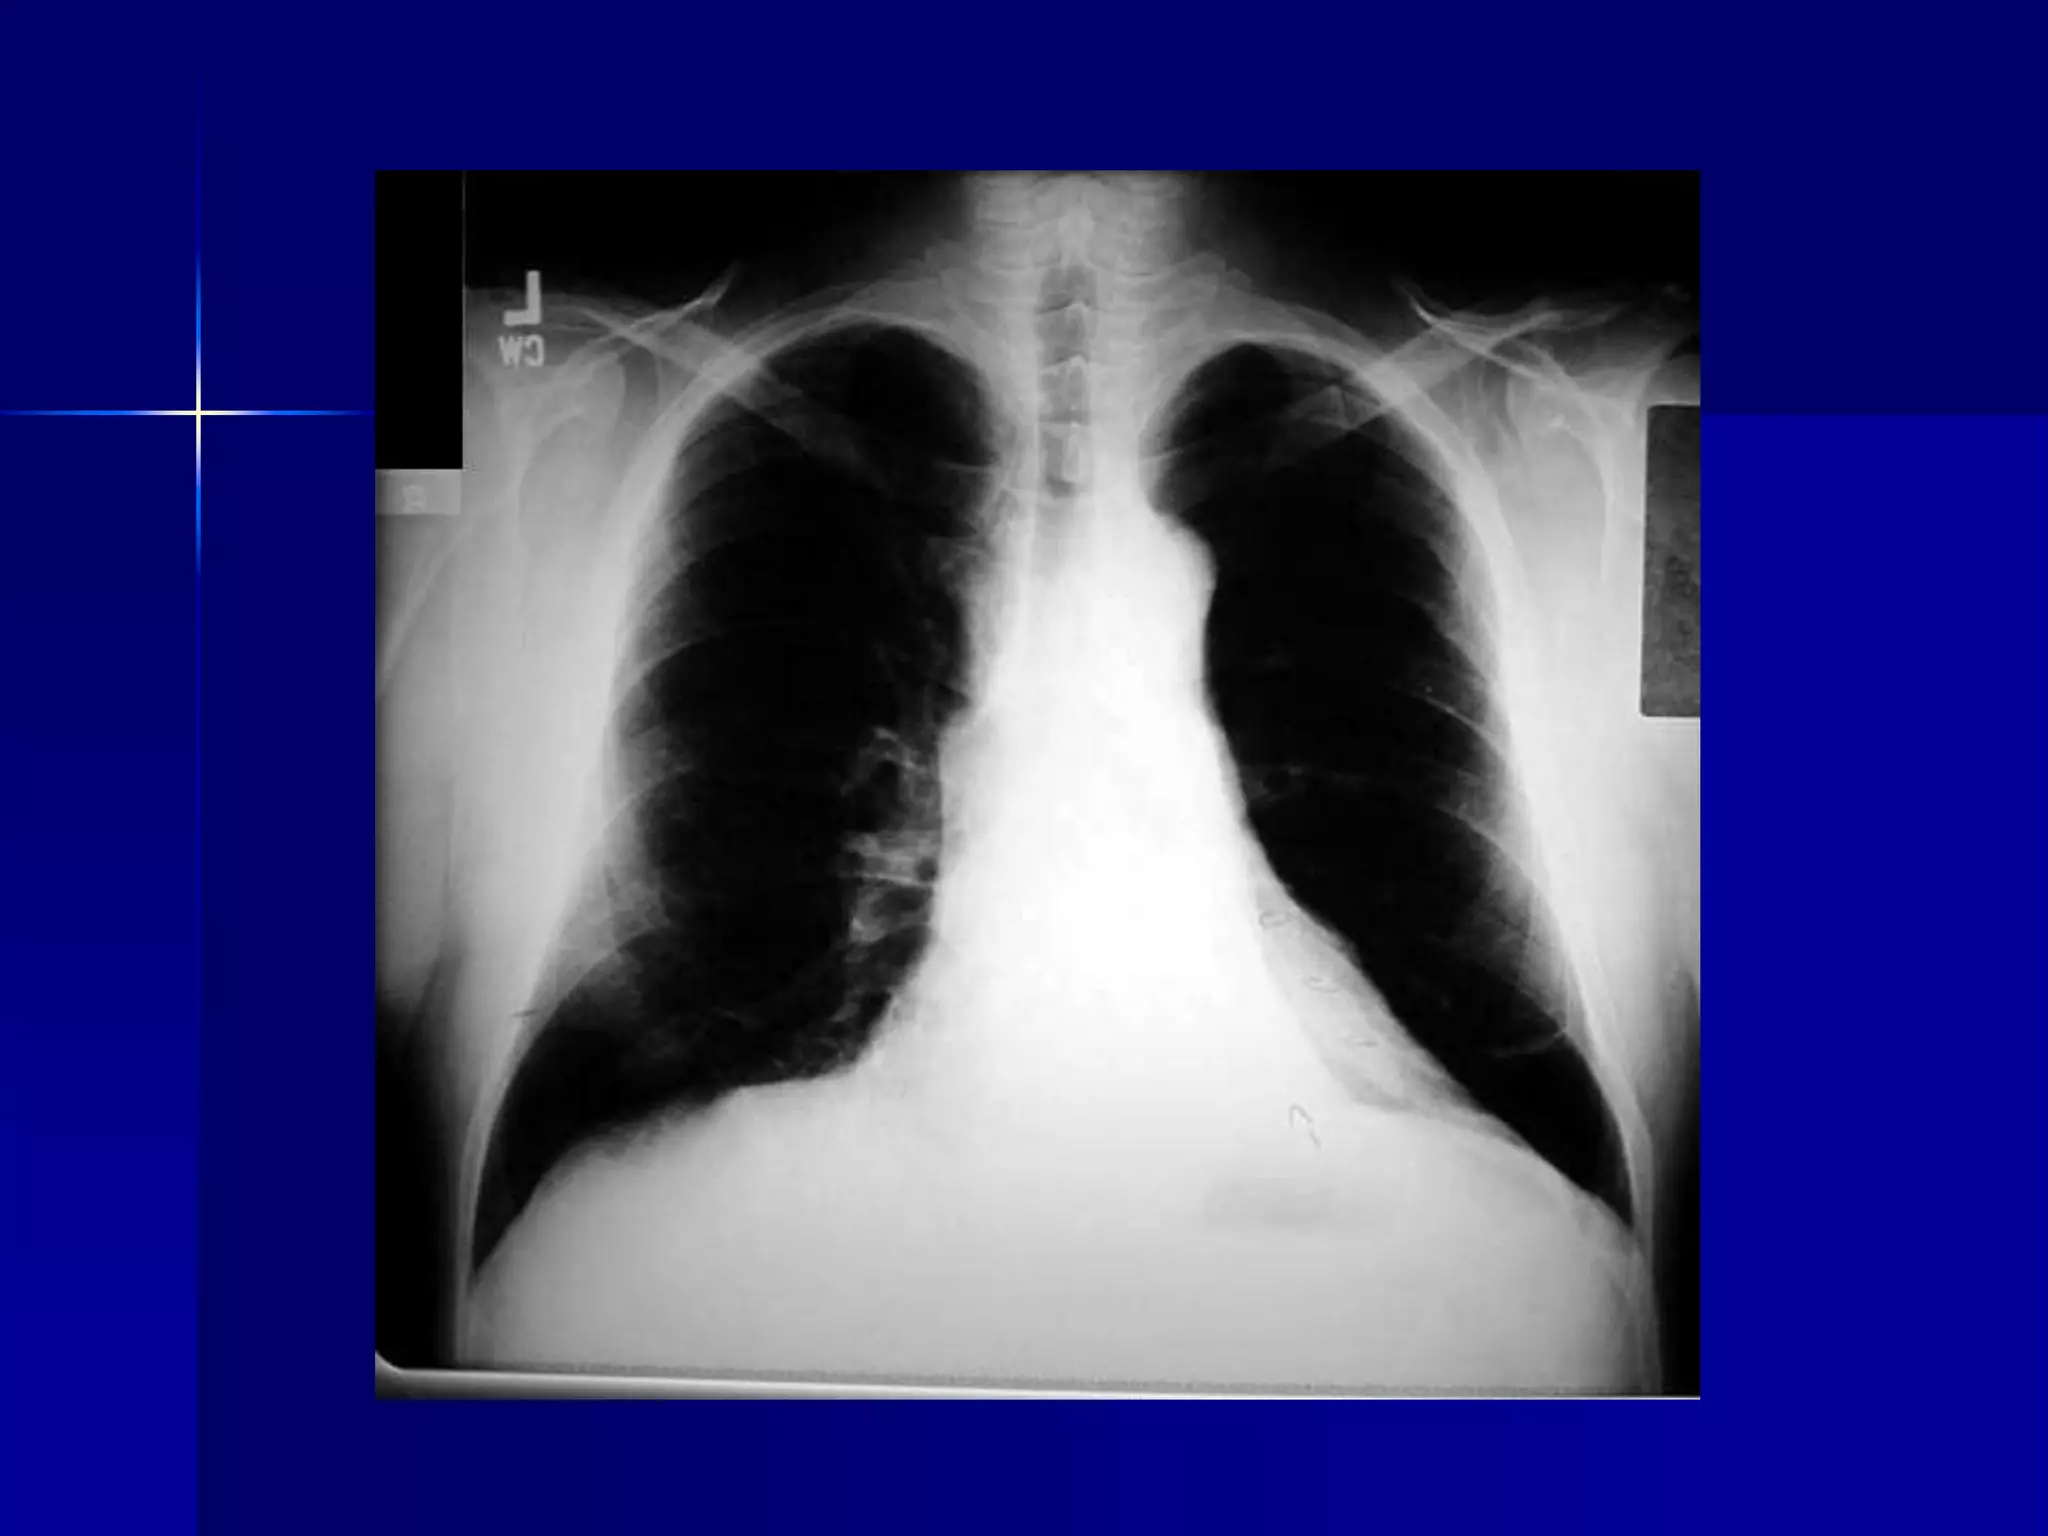

Cystic Fibrosis - Bronchiectasis

 Bilateral diffuse

 Multiple cavities / Bronchiectasis

 Peribronchial fibrosis

 Prominent hilum

 Hyperinflated